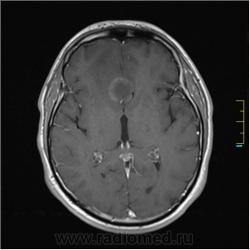

Пациентка направлена на исследование с диагнозом "Гипертонический криз", энцефалопатия неуточненная.

Post-GAD:

частично функционирующая аневризма

Иначе говоря, аневризма с хронической геморрагией, т.к. мы видим фракции крови различного возраста.

По-моему, аневризма с пристеночными тромбами.

Постепенное пристеночное образование тромбов приводит к появлению типичного для аневризмы феномена -слоистости МР сигнала в полости аневризмы. Данная картина демонстрирует слоистый характер тромботических масс в полости аневризмы .Функционрирующая часть имеет низкий сигнал во всех режимах сканирования. Дополнительно-перифокальный отек.

А может более корректно интерпретировать как частично тромбированная аневризма... Уж коь речь идет о фракциях, ну то есть о тромбе по сути.... Ну и плюс перфокальный отек головного мозга (вероятнее цитотоксический+вазогенный).